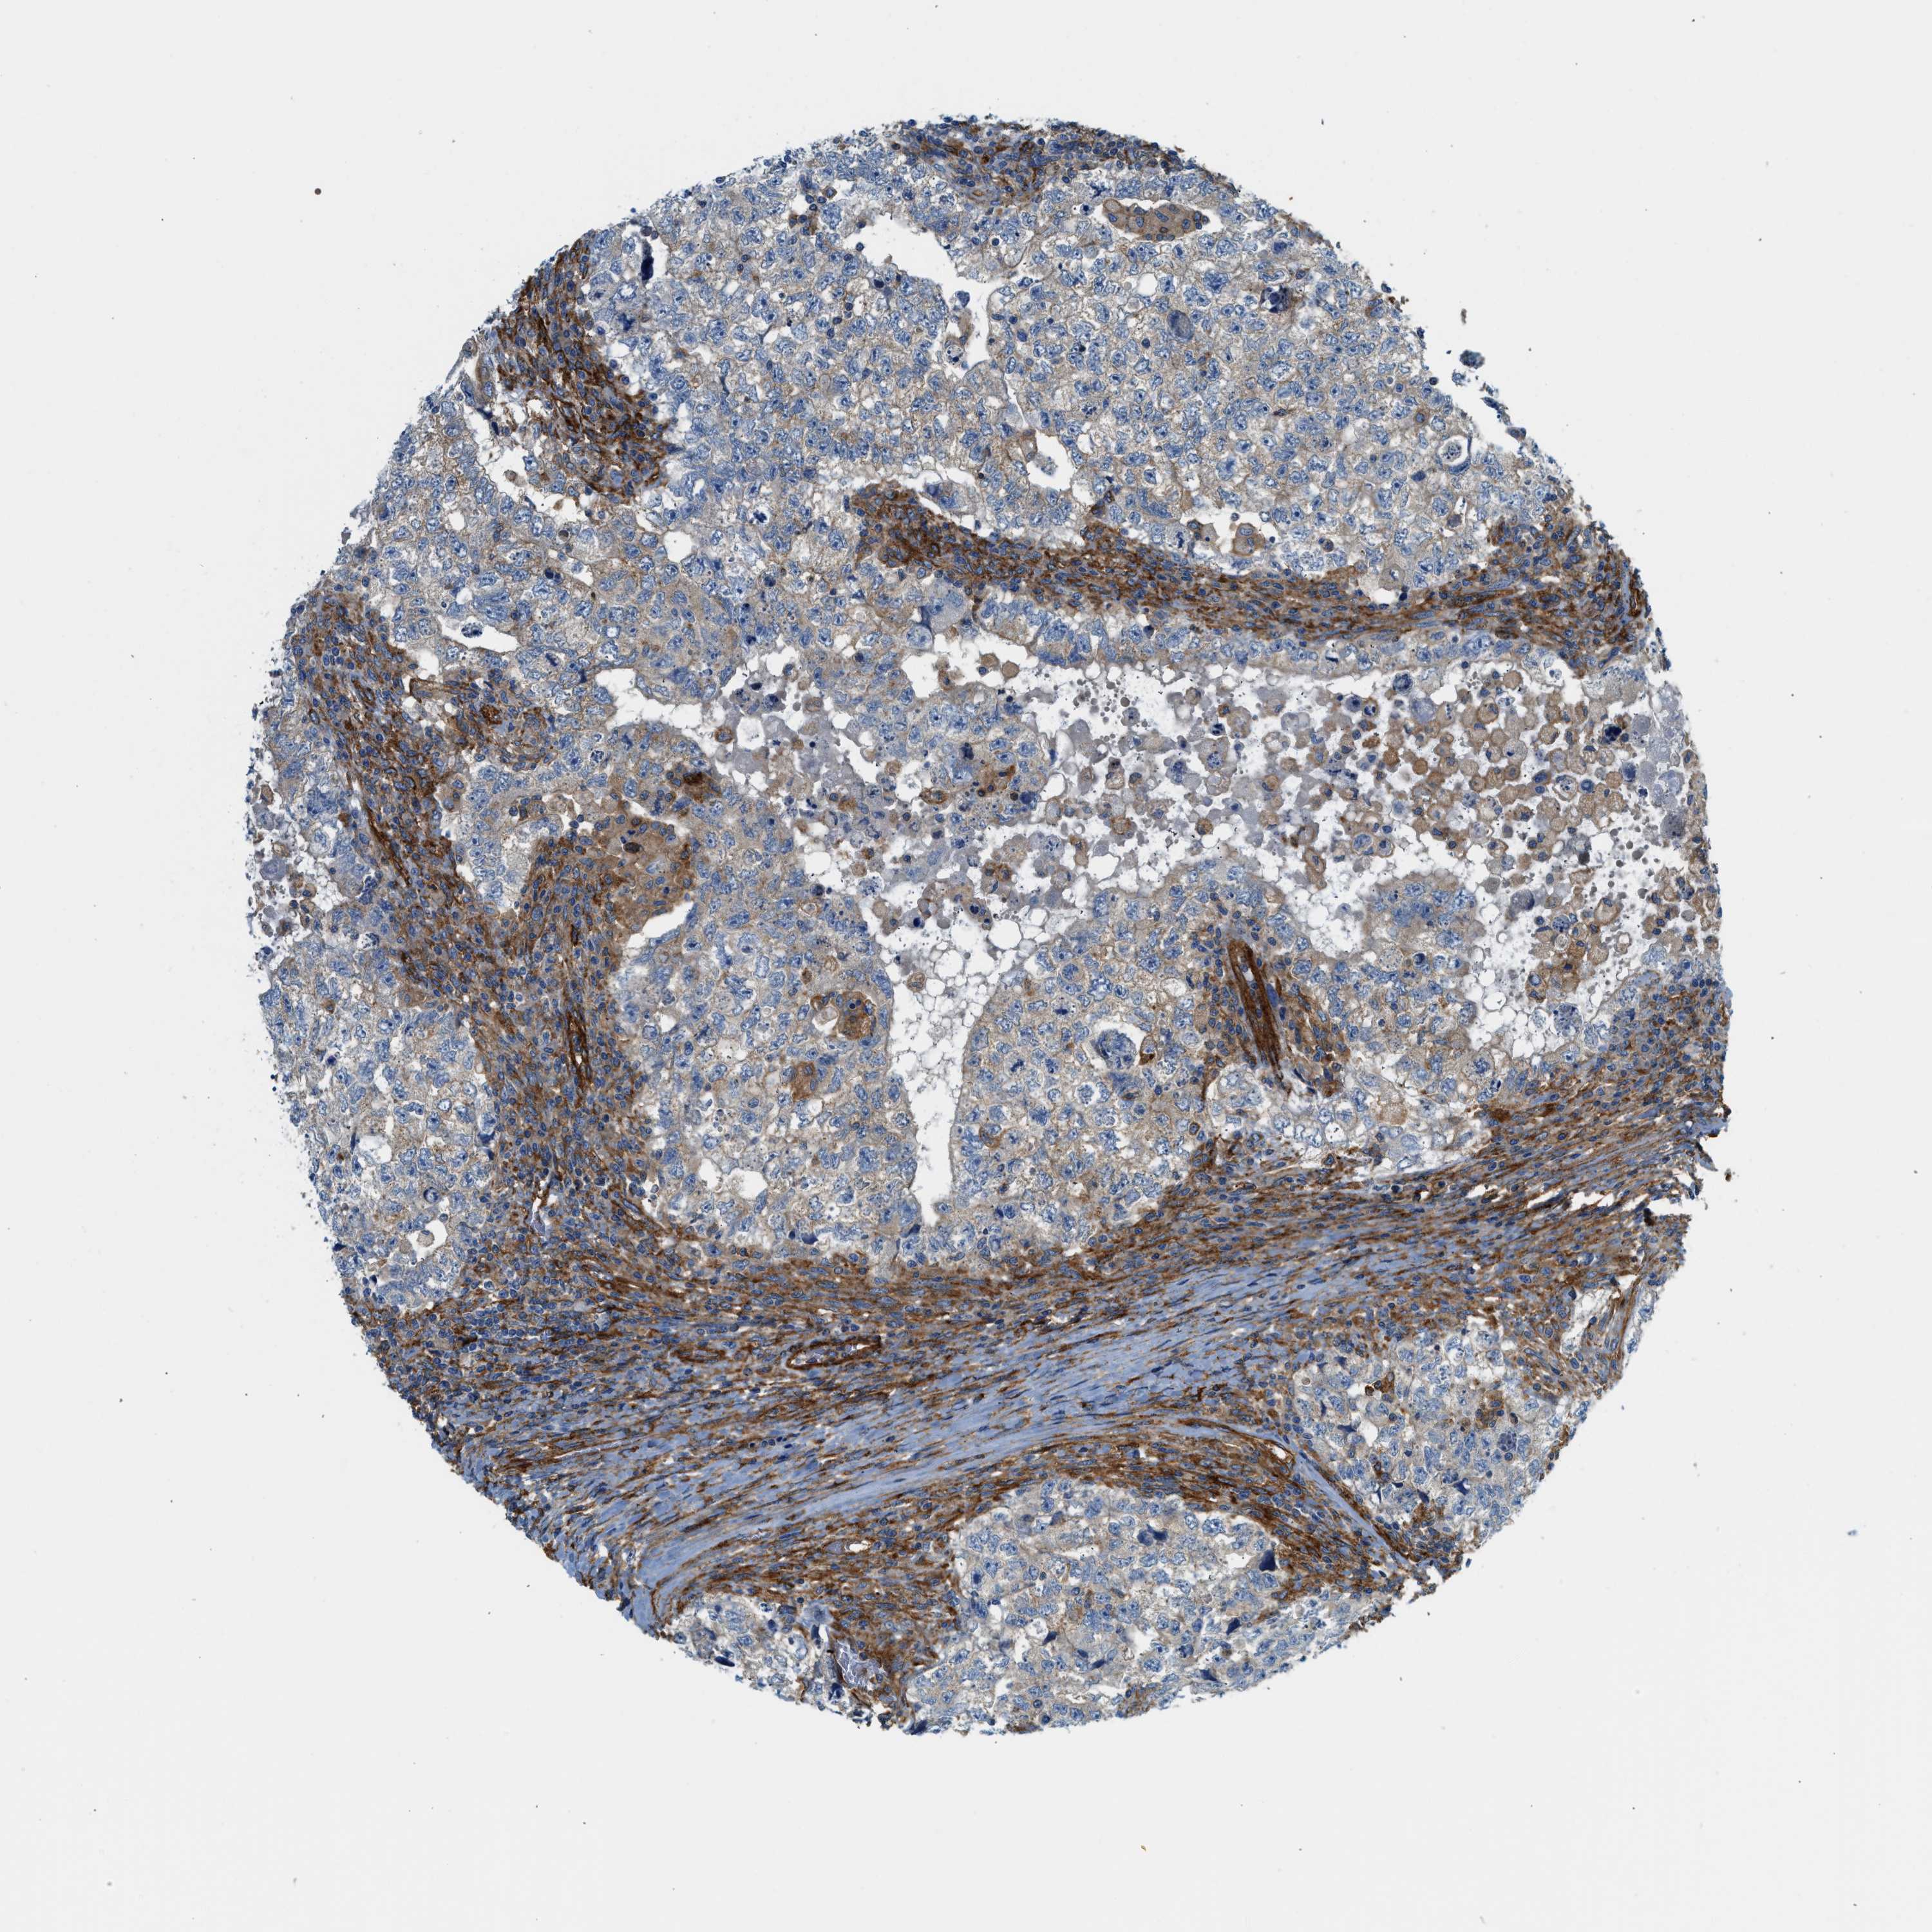

TESTIS CANCER - Protein expressioni

A mouse-over function shows sample information and annotation data. Click on an image to view it in a full screen mode. Samples can be filtered based on level of antibody staining by selecting one or several of the following categories: high, medium, low and not detected. The assay and annotation is described here.

Note that samples used for immunohistochemistry by the Human Protein Atlas do not correspond to samples in the TCGA dataset.

Antibody stainingi

Antibody staining in the annotated cell types in the current human tissue is reported as not detected, low, medium, or high, based on conventional immunohistochemistry profiling in selected tissues. This score is based on the combination of the staining intensity and fraction of stained cells.

Each image is clickable and will lead to virtual microscopy that enables deeper exploration of all samples and also displays staining intensity scores, fraction scores and subcellular localization as well as patient and tissue information for each sample.

Antibody HPA017964

Antibody CAB015334

Antibody CAB016402

Carcinoma, Embryonal, NOS

Seminoma, NOS